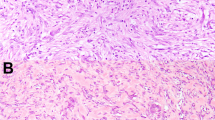

Cranial fasciitis (CF) is an uncommon benign myofibroblastic proliferation involving the soft and hard tissues of the cranium. It typically occurs in the pediatric population with a male predilection (male-to-female ratio 1.5:1). The clinical presentation is usually a rapidly expanding, painless nodule. Bone erosion may be appreciated radiographically. Histopathologic sections of CF show plump, fibroblast-like cells with pale, oval shaped nuclei and prominent nucleoli in a fibrous or myxoid background. Growth is self-limited and surgical excision is considered curative. Due to these features, CF is thought to be a variant of nodular fasciitis (NF). As with NF, CF may mimic a sarcomatous process and pose a diagnostic challenge to clinicians and pathologists alike. Erickson-Johnson et al. identified rearrangements of the ubiquitin-specific protease 6 (USP6) gene in 44 of 48 cases of NF. MYH9 was the fusion partner in 12 of these cases. To date, the molecular profile of CF has not been studied. Here we present the molecular findings in three cases of CF identified at our institution. Each case was subjected to fluorescence in-situ hybridization with appropriate negative controls. Two of three cases were positive for the USP6 gene rearrangement. The third case failed to hybridize, likely related to nucleic acid damage secondary to decalcification. Negative controls did not demonstrate the genetic rearrangement. These findings warrant further investigation of the USP6 gene rearrangement in CF, as it may prove helpful as a diagnostic adjunct in challenging cases.